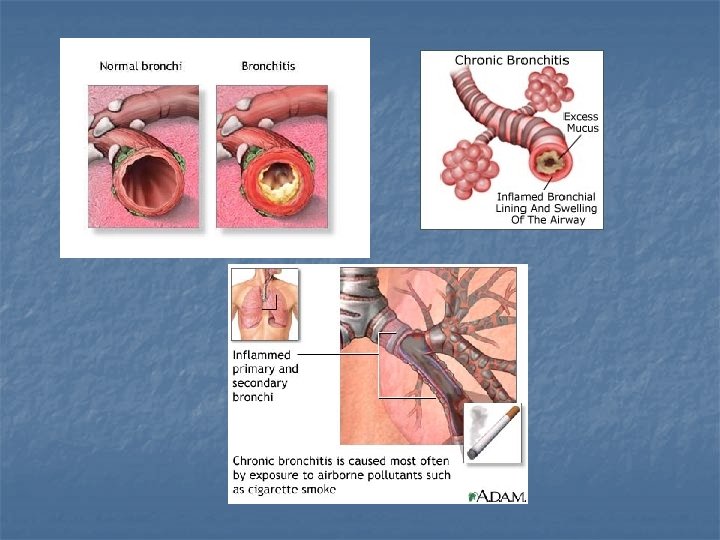

BRONCHITIS An infection of the bronchi 2 types: 1. Acute – caused by a bacteria - treated with antibiotics n

BRONCHITIS 2. Chronic – long term - usually caused by an irritant – ie smoking - cilia become damaged and can’t clear debris - treatment – quit smoking